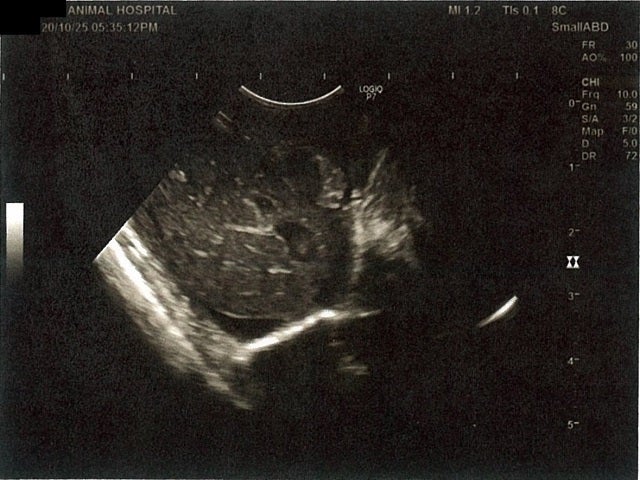

《心臓周りの胸部以外の全ての腹部で腹水がみられるとの診断です》

大網という部分で内臓を包む膜のようなものです。その周りに腹水が溜まっています。

左腎臓周りに腹水が確認できるエコー写真